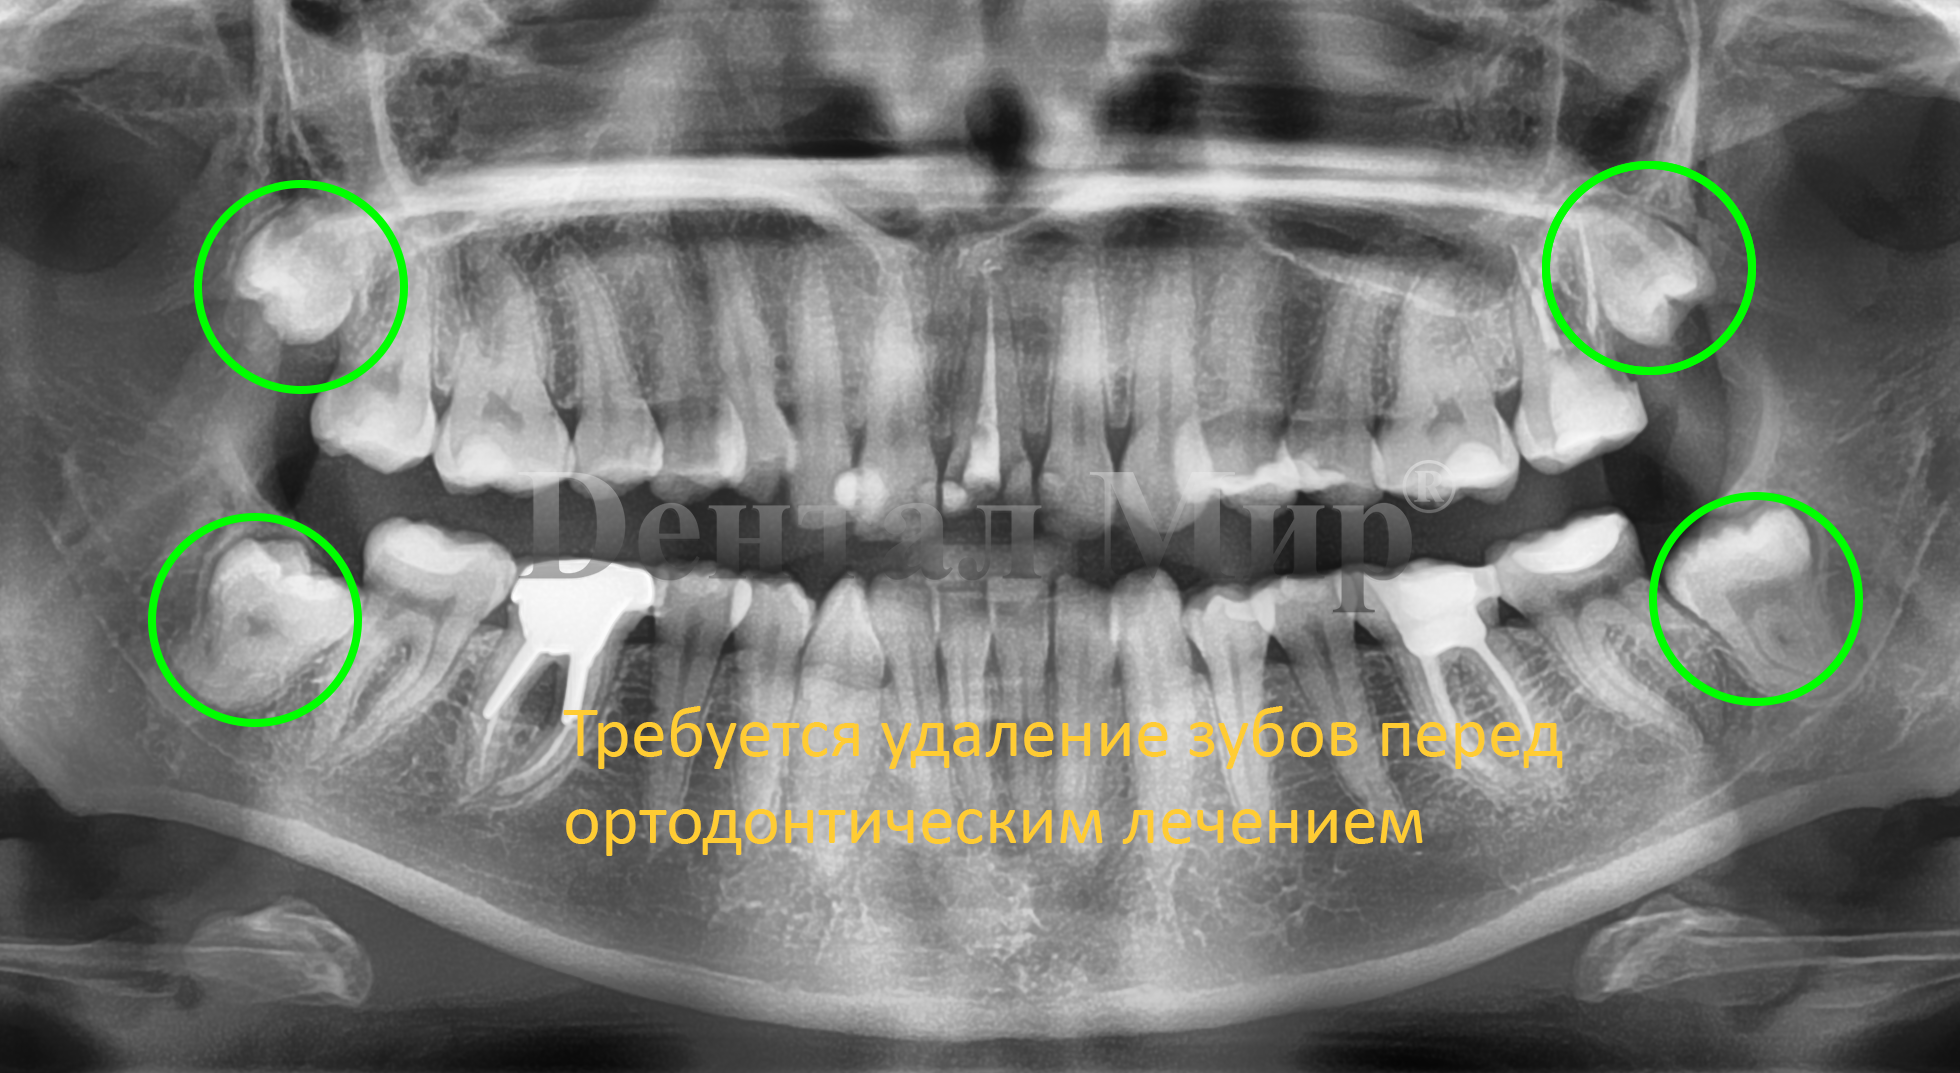

Исправление прикуса. Этот вопрос один из немногих, требующих детального рассмотрения почти всеми специалистами клиники. Ортодонтическое лечение всегда комплексное, т.к. кроме выставления самих зубов в зубной ряд, требуется установка правильной окклюзии, а в процессе перемещения часто требуются вмешательства терапевта и гигиенические процедуры. Поэтому на консультации могут присутствовать кроме ортодонта, еще и стоматолог терапевт, пародонтолог и стоматолог ортопед.